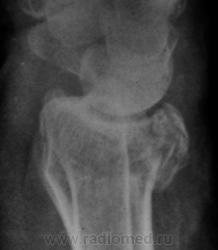

Травма. Пациент направлен на рентгенографию лучезапястного сустава.

луча в типичном месте. А вот шиловидный отросток похоже тоже сломался?